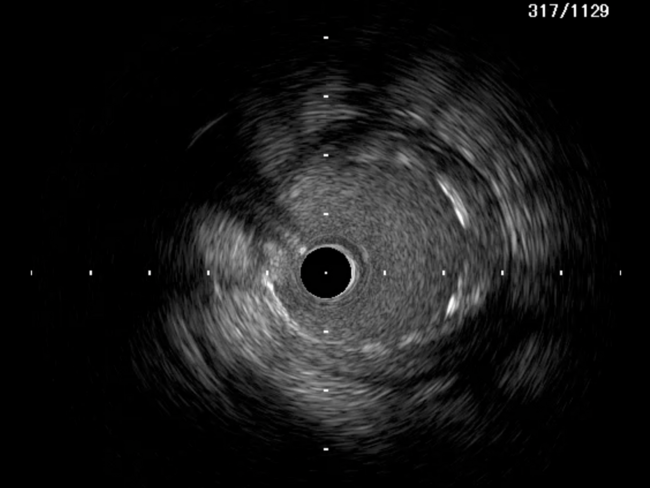

A 51-year-old man presented with stable angina and previously failed right coronary artery (RCA) CTO PCI. During RCA CTO PCI (Figure 1), the wire was inserted into the extraplaque space (Figure 2, Video 1). Intravascular ultrasound (IVUS) showed a hematoma (Figure 3A, Video 2). Live 3-dimensional tip detection IVUS wiring was successful (Figure 4, Video 3). A FineCross microcatheter (Terumo) was placed over the first wire into the extraplaque space and blood was withdrawn by connecting a negative indeflator to the microcatheter. Stents were deployed (Figure 5) and postdilated. Post-IVUS showed almost complete resolution of the hematoma (Figure 3B, C; Video 4) with good results (Figure 6, Video 5).